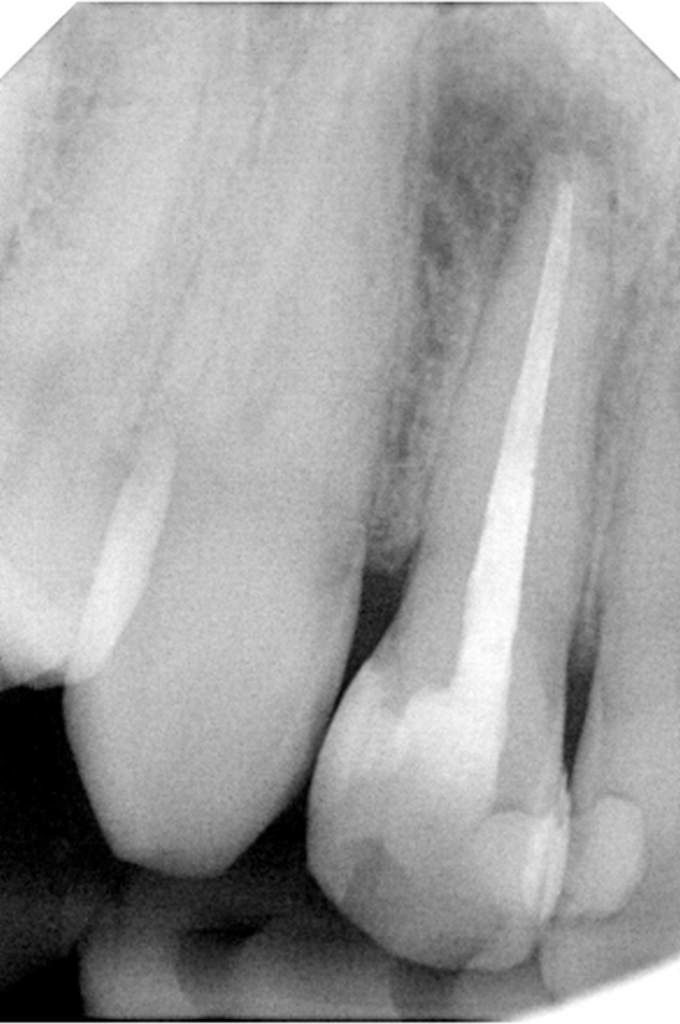

Αρχική εικόνα δοντιού

Εικόνα δοντιού μετά από επανάληψη θεραπείας

Η επανάληψη μιας ενδοδοντικής θεραπείας δεν σημαίνει και τη διάσωση τελικά του δοντιού. Η δυναμικότητα των παθογόνων αναερόβιων μικροβίων που έχουν αναπτυχθεί στο σύστημα των ριζικών σωλήνων με την συνεπακόλουθη καταστροφή των περιακρορριζικών ιστών καθιστά πολλές φορές αδύνατη τη διατήρηση του δοντιού, ακόμη και με τον συνδυασμό της μικροχειρουργικής ενδοδοντίας.